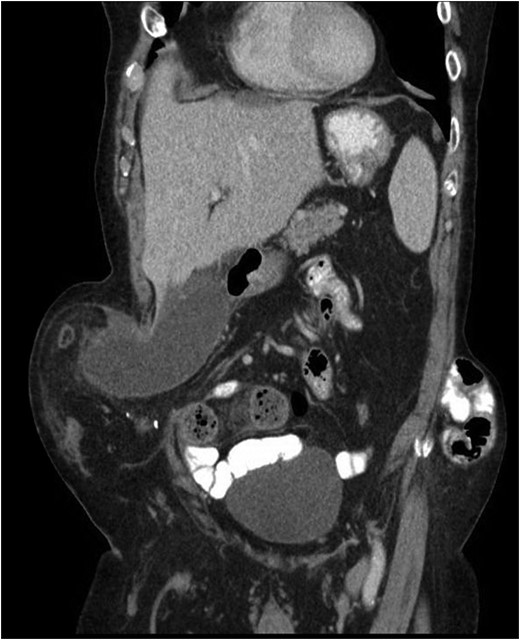

Our patient is an 89-year-old male with a history of a Hartmann’s procedure (2006) for Crohn’s disease of the sigmoid colon followed by a reversal of the colostomy with a diverting loop ileostomy (2008). Due to his comorbidities and age, the patient declined further surgery to reverse his loop ileostomy. Most recently, the patient presented to the emergency room with no ostomy output for the past 14 h, nausea and frequent burping. He reported a burning sensation around his ostomy. His physical examination revealed a large parastomal hernia in the right hemiabdomen and associated tenderness in the right upper quadrant, with no overlying skin changes. His white blood cell count was 8.1 (82.4% neutrophils), and he had normal liver function tests. A computed tomography (CT) scan of the abdomen and pelvis revealed a large parastomal hernia with a wide neck containing a distended gallbladder concerning for acute cholecystitis, as well as a small bowel obstruction with a transition point at the level of the hernia (Figs 1 and 2). A previous CT scan showed the same hernia with a nondistended gallbladder and non-obstructed bowel entering and exiting the stoma (Fig. 3).

Acute cholecystitis causing a small bowel obstruction within a parastomal hernia. Arrow points to transition point.

CT from current admission with distended gallbladder consistent with acute cholecystitis.

CT from May 2017 with decompressed gallbladder and unobstructed bowel.